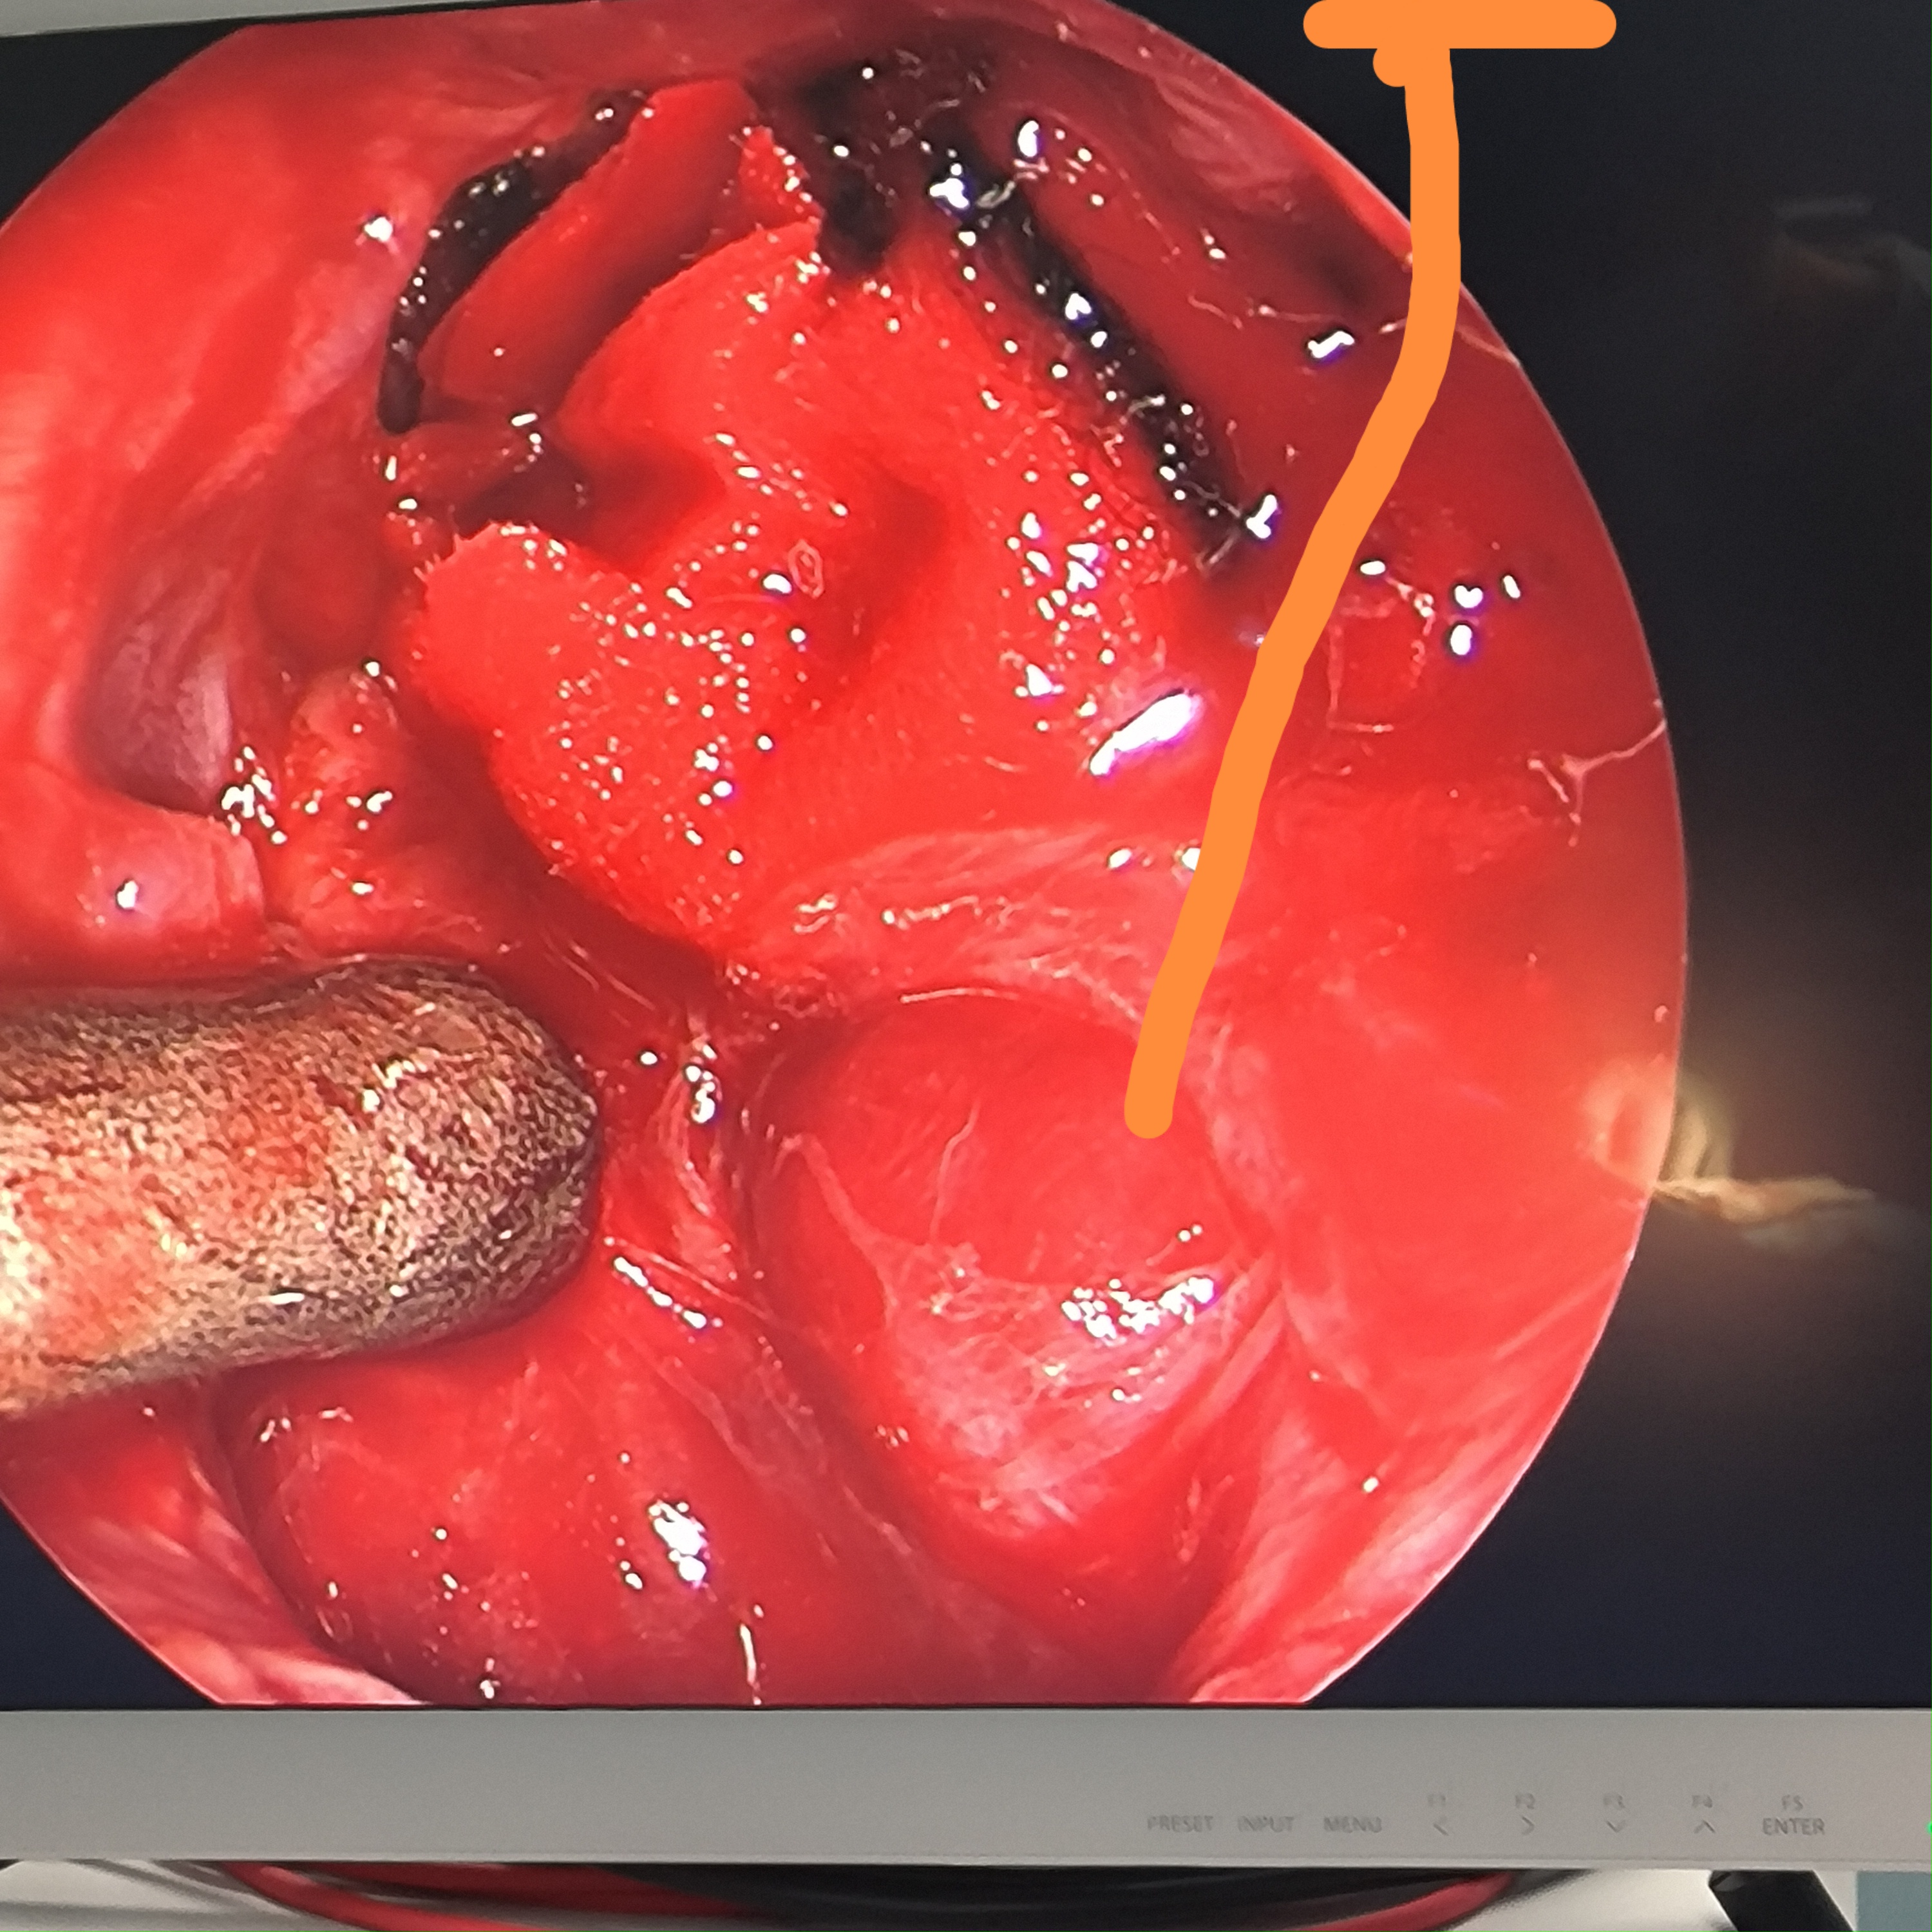

颈椎哑铃型神经纤维瘤,椎间孔汇合,安全又便于操作~